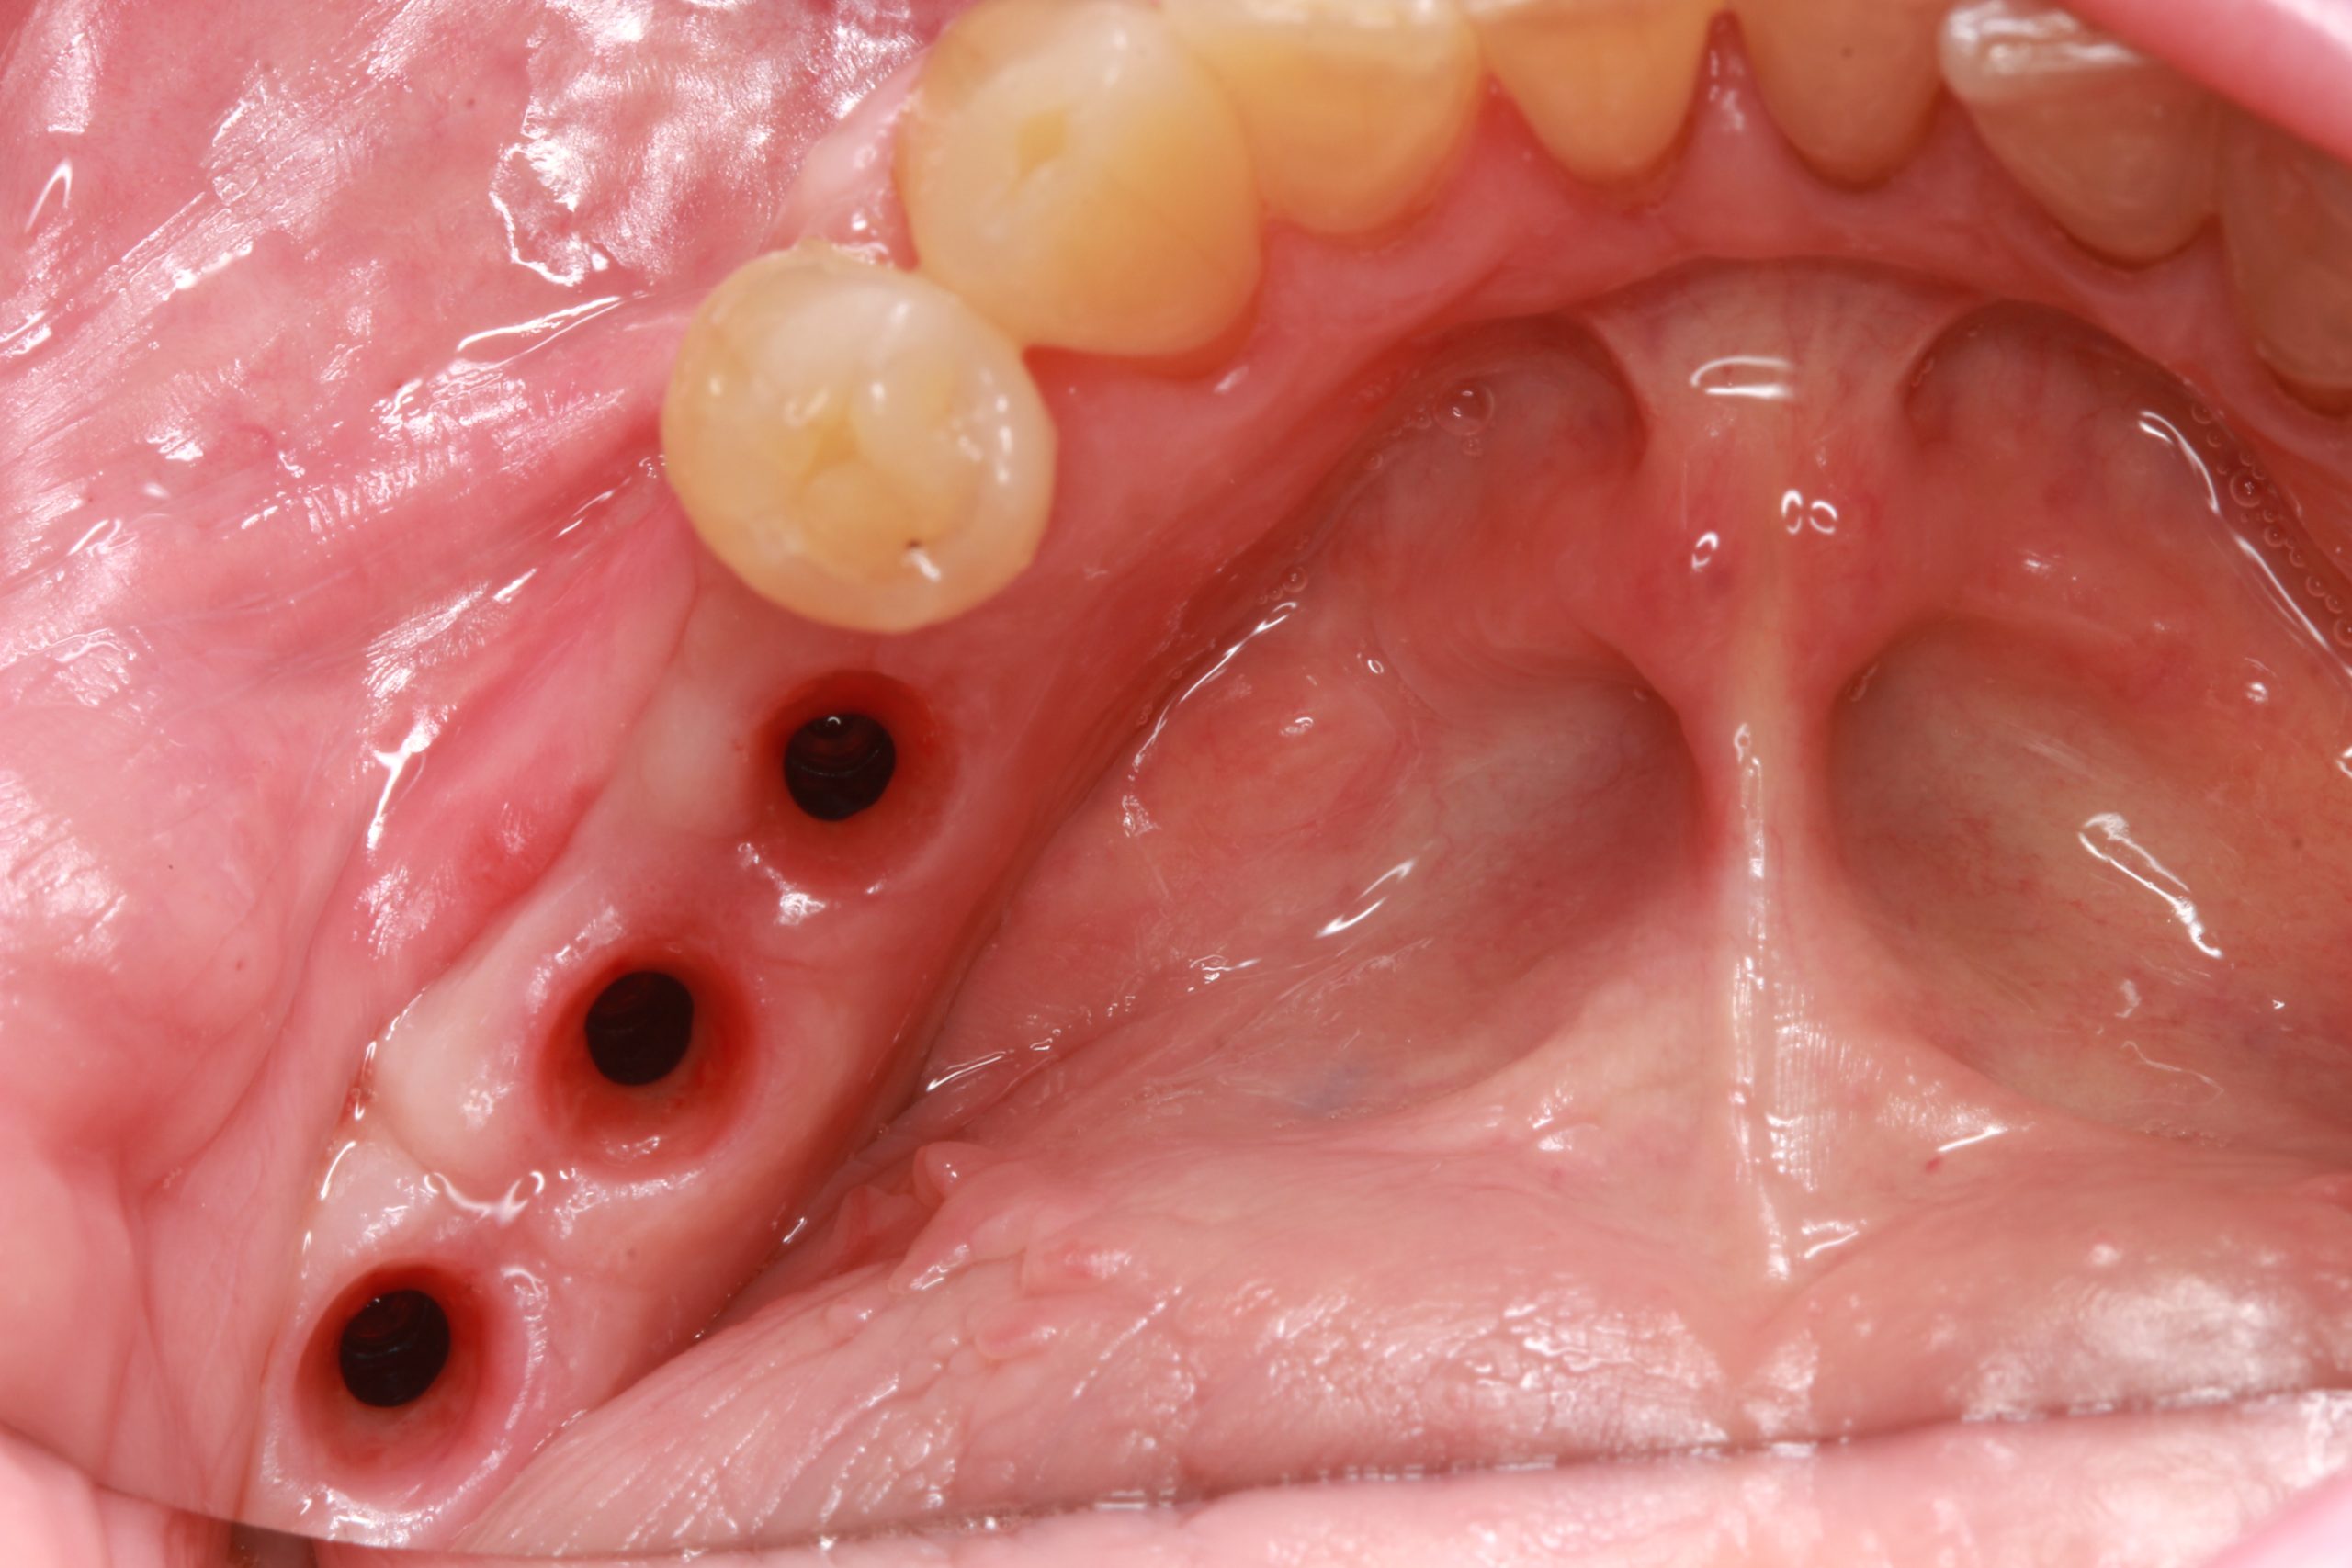

After three months, the implants were exposed, and the impression was taken.